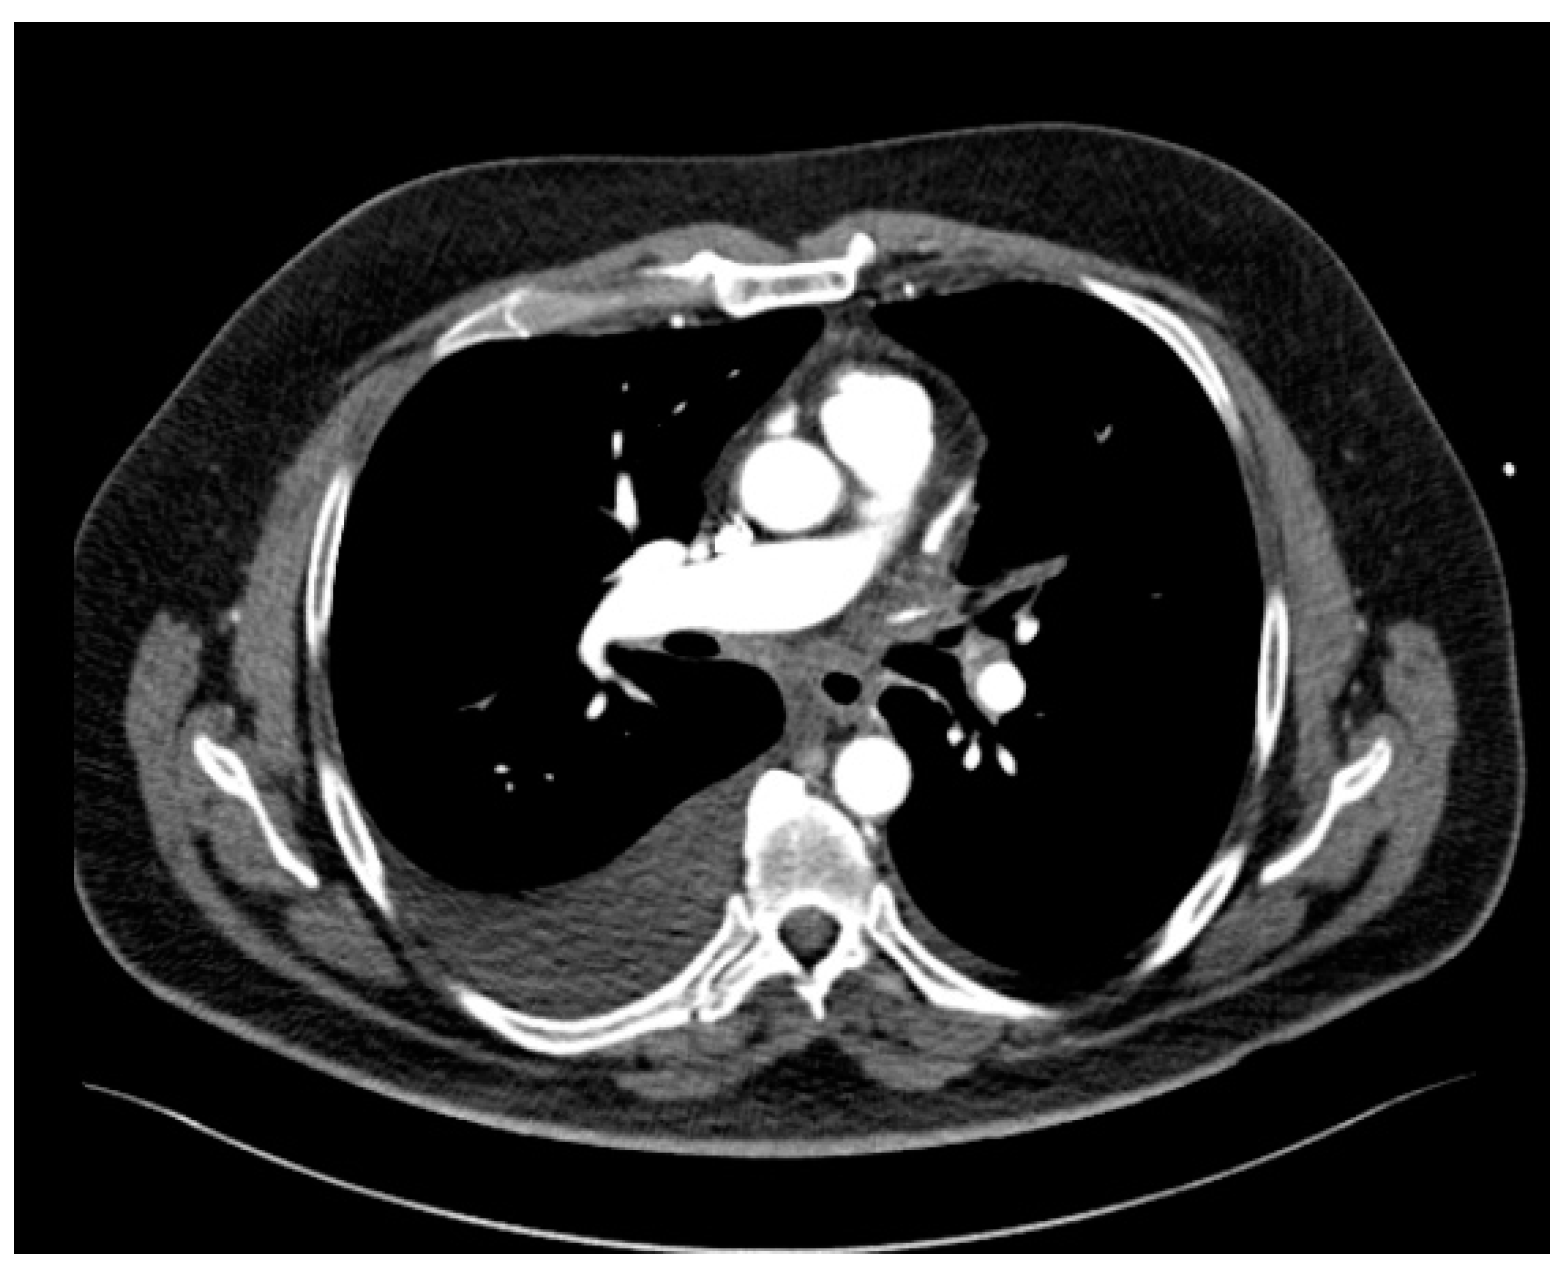

The patient also presented bilateral pleural effusion (40 mm on the right side and 7 mm on the left side) and a soft tissue attenuation obliterating normal mediastinal fat planes and encasing both the PVs and the esophagus posterior to the left atrium, an aspect suggesting fibrosing mediastinitis probably caused by the severe inflammation induced by radiofrequency ablation associated thermal injury (Figure 3). As for the parenchymal findings, a global mosaic attenuation was present, especially in the right middle lobe, together with a ground-glass opacity in the apical segment of the left lower lobe. The parenchymal findings were mostly consistent with pulmonary veno-oclusive disease and an area of hemorrhagic infarction.

Figure 3.

Axial CT image of the mediastinum revealing soft tissue attenuation around the esophagus suggestive for fibrosing mediastinitis.